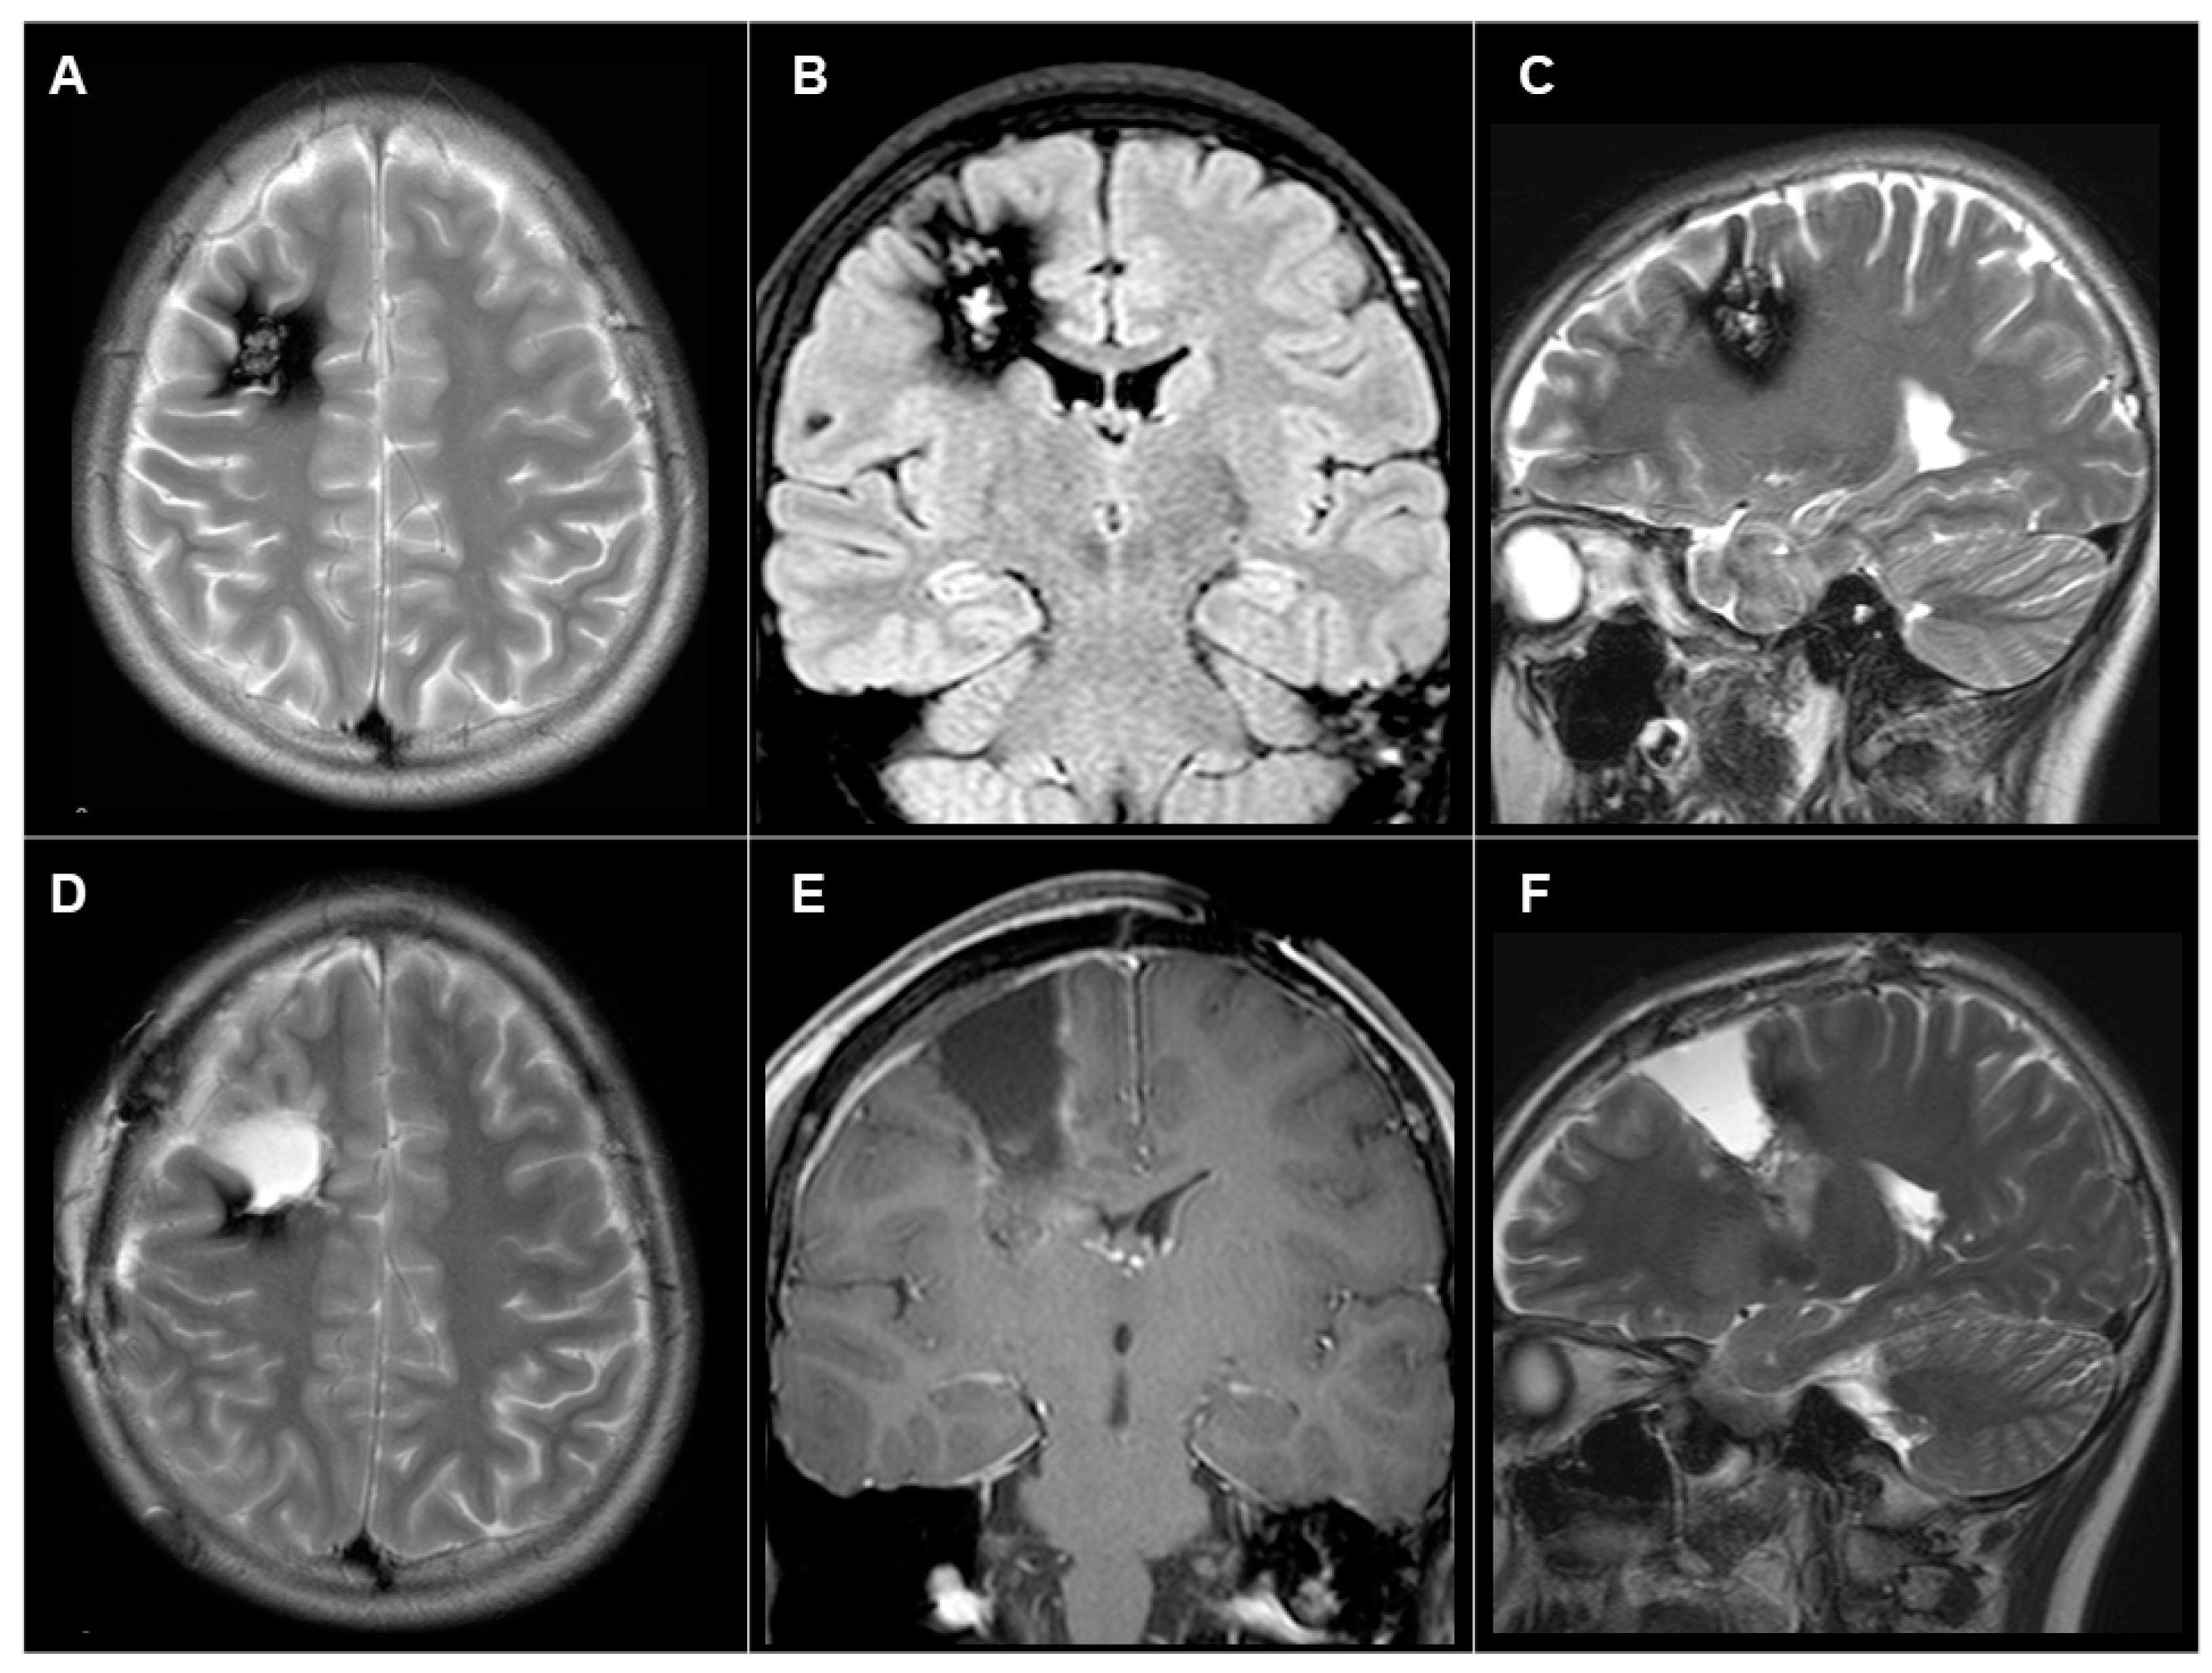

3.3.1. Patient #1 (AWC#1) (Figure 2)